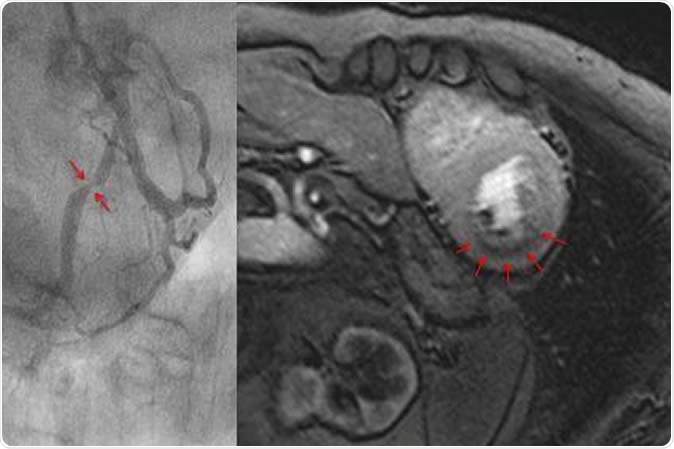

Measuring blood flow in the myocardium with magnet resonance imaging (top). The dark area in the myocardium (arrows) shows a pronounced reduction of blood flow. The cardiac catheterization of the same patient (bottom) shows a clear constriction of the artery. Image Credit: Eike Nagel, Goethe University